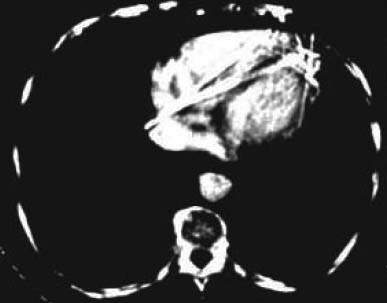

図2. 臨床例第1号.前頭葉の嚢胞性腫瘍[1]

異常像:密な組織,線維性組織は正常組織より高濃度である.石灰化病変は著しく高濃度で,髄膜腫,低悪性度星細胞腫などは高濃度となる.脳内出血は凝固が開始すると高濃度になる.イオタラム酸ナトリウム20~40mlを静注後にスキャンすると,様々な腫瘍の濃度に上昇が認められ,髄膜腫は特に著しく上昇した.組織濃度の低下は数多くの病態で認められ,梗塞,悪性腫瘍の壊死,嚢胞,変性,浮腫などが主たるものである.

【解説】Hounsfieldの共同研究者で,臨床面を担当した医師Ambroseによるもので,現在でも基本とされるOM線による頭定位法,検査手順の解説に続いて,脳の正常例,異常例が多数供覧されている.

高吸収,低吸収を示す病変の例がそれぞれ挙げられているが,基本的な疾患,病態の所見について,その組織背景を含めてこの時点で既に的確に把握されている点は驚異的である.また既にヨード造影剤も使用されている.体動による画質劣化,後頭蓋窩など,骨と近接した領域の診断が難しいことなどについても触れられている.まだ画像の濃淡に関する知識が蓄積していないこともあり,X線減弱係数のプリントアウトを参照して診断の一助としている点は興味深い.